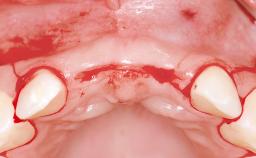

A 38-year-old woman presented with an esthetically unacceptable fixed partial denture replacing teeth 11, 21, 22. She had lost these teeth due to trauma when she was a child. The patient was not in pain but very concerned based on her previous experience that dental treatments had never satisfied her esthetic expectations. She was in good general health and reported no regular medications. No periodontal disease was noted despite the fact that the buccal flange of the prosthesis impeded cleaning of the tooth abutments. The patient did not smoke and complied with home maintenance requirements, as evidenced by her good oral hygiene status.

Bone Augmentation | Horizontal|Simultaneous|Staged |

Augmentation Materials | Autogenous block(s)|Xenogenous|Membrane |

Soft Tissue Grafting | Staged |